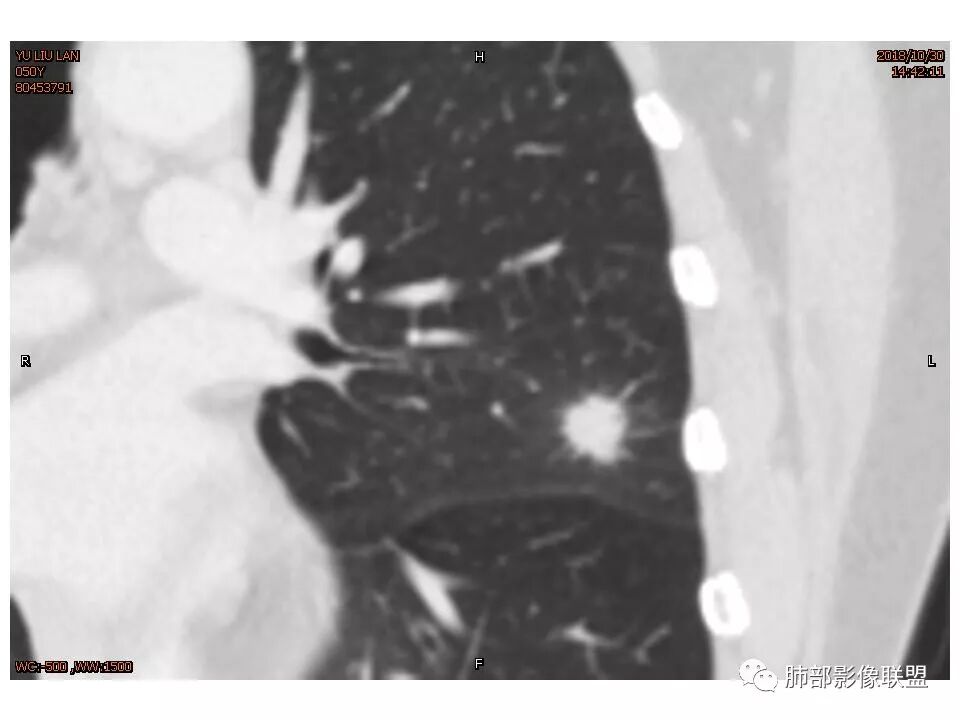

定位左舌,结节,有晕,晕中软毛刺,长毛刺与胸膜牵拉,收缩明显,部分呈方形,明显强化及延迟强化,有支气管近端进入远端阻塞,部分呈鬼脸

鉴别:腺癌 牵拉斜裂,有动静脉相连,

左肺上叶结节,部分边缘膨隆,边缘毛刺,斜裂牵拉,增强中度强化,血管穿行,血管略增粗。考虑肺癌,腺癌可能性大,鉴别肉芽肿性炎

左肺上叶结节影,病灶周围呈磨玻璃样改变边缘见毛刺、分叶及胸膜牵拉,增强扫描病灶明显强化,病灶未跨叶间裂,考虑炎性病变,待除外小腺癌。

结节样病灶,u型征,病灶内可见细支气管管,增强可见血管进入,略增粗,病灶周围有晕,有软毛刺,局部叶间胸膜有牵拉,考虑良性炎性病灶,抗炎后复查。

左上肺结节 周围磨玻璃边缘模糊 结节周围有短及长毛刺 虽有收缩力 但病变边缘收缩较多 长毛刺对邻近外侧胸膜没什么收缩 增强有延迟强化 进入血管稍增粗 首先考虑炎性 感觉炎症吸收过程中也可以这样 腺癌待排

细小毛刺,梳状平行,周围边缘模糊晕,血管未收侵犯,支气管未见牵拉扩张,多条淋巴道与胸膜相联,倾向于炎性病变

1.胸膜下略不规则实性密度结节影,孤立,缺乏典型深分叶,可见淡薄边界模糊磨玻璃晕,可见相对细长软毛刺。

2.如南边老师分析,病灶缺乏边缘膨隆优势,甚至部分平直内收。

3.病灶收缩力不强,整体强化程度不显著。

4.综上,病灶更符合炎性,如隐球菌感染等,而不大符合肺腺癌。具体到机化性肺炎略有些出乎预料。